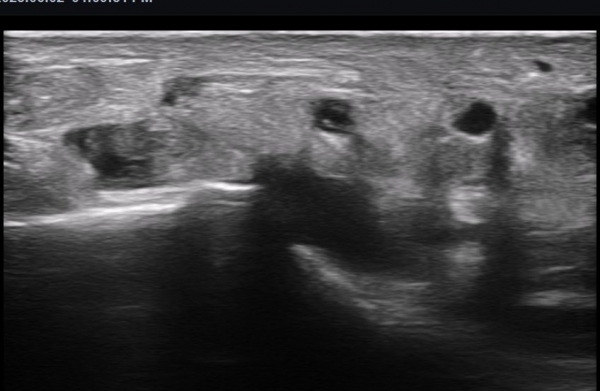

ºñº¹½Å°æ Á¾´Ü¸é°Ë»ç(»çÁø 14, 15)¿¡¼­ ºñº¹½Å°æÀÇ Àü¹ÝÀûÀÎ Àú¿¡ÄÚ ºÎÁ¾°ú ºñº¹½Å°æ ½ÉÃþÀ¸·Î ´Üºñ°ñ°Ç³»

³¶Á¾¼º º¯º¯ÀÌ °üÂûµÈ´Ù.